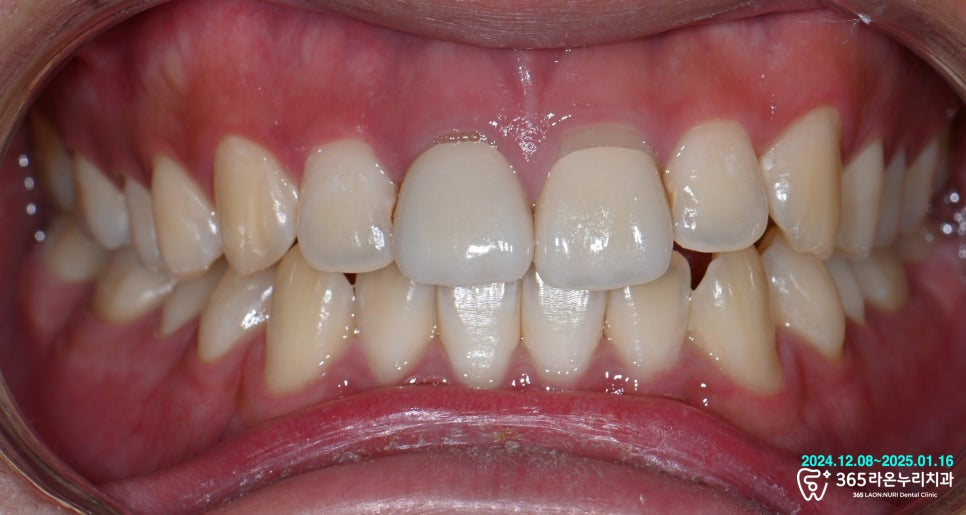

이제 최종 크라운을 제작할 차례입니다.

쉐이드 테이킹(Shade taking)을 통해

치아의 색을 신중하게 결정했습니다.

그렇게 결정한 색을 토대로,

지르코니아 크라운을 올려

완성해드렸습니다.

기존 보철은 치아 형태가 각각 다르고

순측 마진이 맞지 않아

예쁘지 않았습니다.

그렇기 때문에 오산역 치과 에선

앞니 지르코니아 제작 과정에서

색과 모양에 많은 공을 들였습니다.

앞니인 경우 많이들 지르코니아를 선택하시는데요.

자연스러운 앞니를 위해 지르코니아 보철에

세라믹으로 표면 질감을 더하여

자연 치아와도 조화롭게 보일 수 있도록

제작해드렸습니다.

그 결과, 심미적으로

자연스러운 보철이 제작되었습니다!